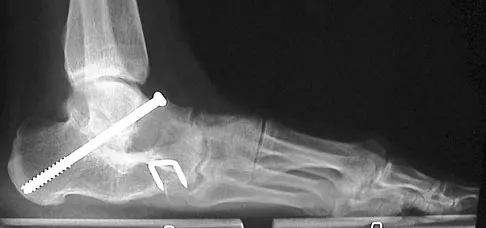

Figures 33a and 33b show the radiographs of a 10-year-old girl who reports a 4-month history of medial foot pain after she was kicked while playing soccer. The pain is worse with activity and partially relieved by rest. Examination reveals tenderness directly over a prominent navicular tuberosity. Management should consist of

Explanation

An accessory tarsal navicular is located at the medial tuberosity of the navicular bone. Nearly all children and adolescents who have a symptomatic accessory tarsal navicular bone become asymptomatic when they reach skeletal maturity. Initial management should include activity restrictions, shoe modification to avoid pressure over the prominent navicular, and non-narcotic analgesics. Although anecdotal, the use of arch supports may be helpful. When pain is refractory to these methods, a short period of cast immobilization may be useful. Surgery should be reserved for patients who have disabling symptoms despite a prolonged period of nonsurgical management. When surgery is indicated, simple excision of the accessory navicular is recommended. Sella EJ, Lawson JP, Ogden JA: The accessory navicular synchondrosis. Clin Orthop 1986;209:280-285.